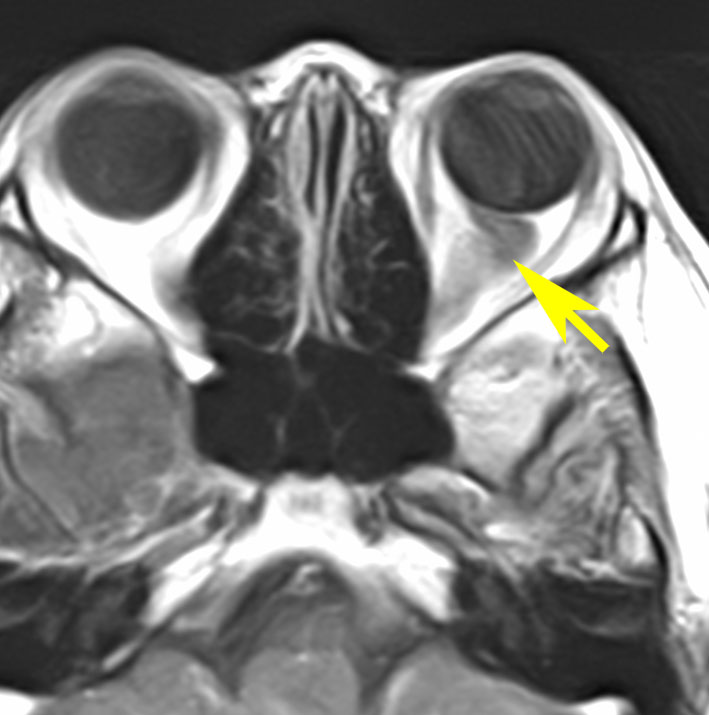

幼児の視路の毛様粘液性星細胞腫です。T2強調画像(左側)で白く高信号に写るのが特徴です。ガドリニウム増強ではまだらになっていますが,均一に真っ白に高信号になることも多いです。乳幼児のものは,ドロドロに柔らかい腫瘍です。

眼窩内単視神経膠腫

1歳児の左眼窩内単視神経膠腫です。左目は手動弁程度ですから,全摘出しました。まぶたの動きと眼球運動は温存しました。この例に何年も化学療法を続けるのは馬鹿げています。

左の写真は,左眼窩内腫瘍,右の写真は,頭蓋内の正常左視神経です。

生後7カ月の幼児です。目が揺れるようになり(振り子様眼振)眼科を受診して腫瘍が発見されました。小児脳腫瘍の治療ができる病院へと紹介されました。

1ヶ月後にまたMRI検査がされました。乳児ですから検査にも麻酔が必要です。腫瘍は明らかに大きくなっています。左視神経から視索の腫瘍化が著しいので右側だけかすかに視力が残っているかもしれません。視力は明かりがわかる程度(明暗弁)と評価されました。